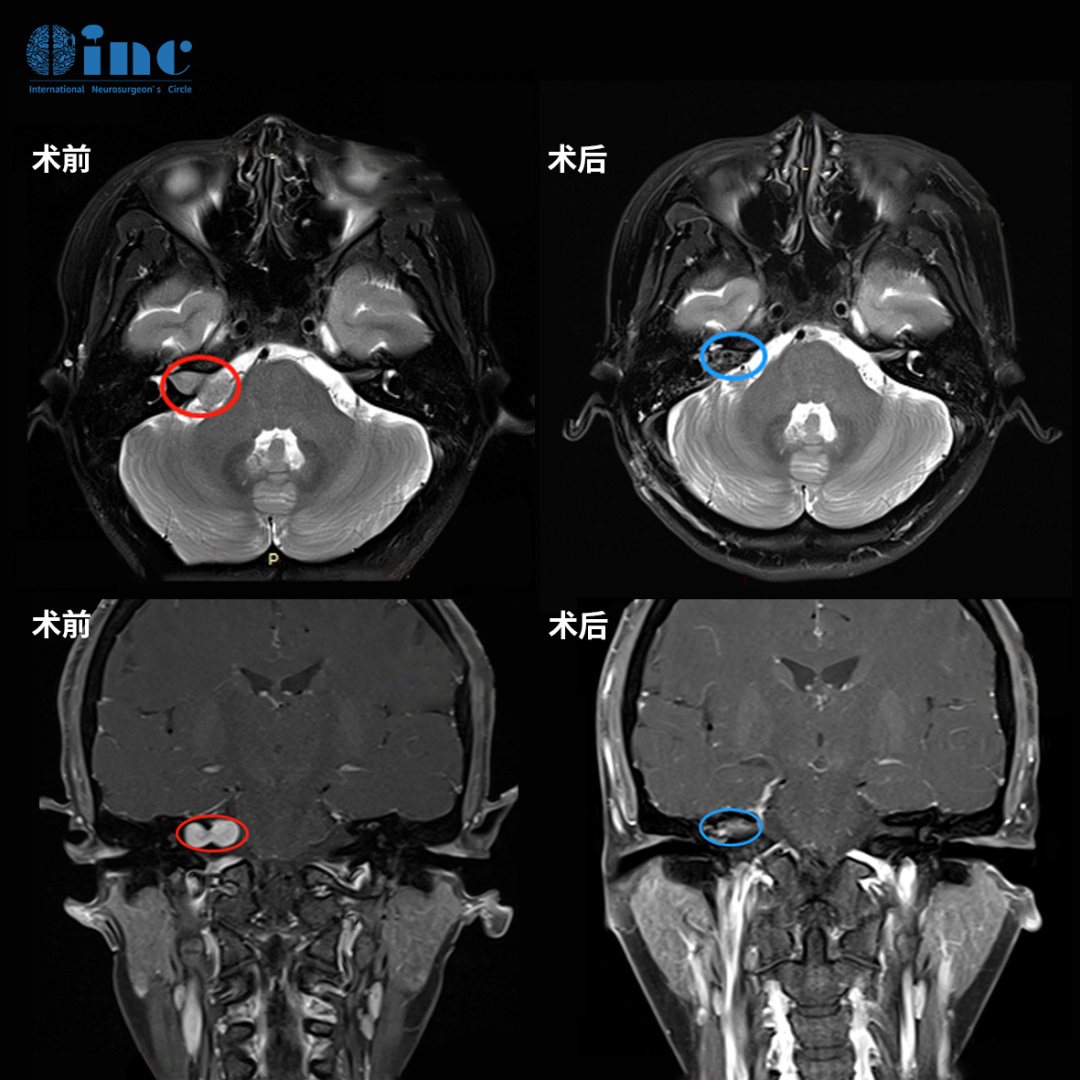

1999年7月因頭痛查出顱咽管瘤,并在2000年1月及4月的復(fù)查中發(fā)現(xiàn)腫瘤不斷生長。